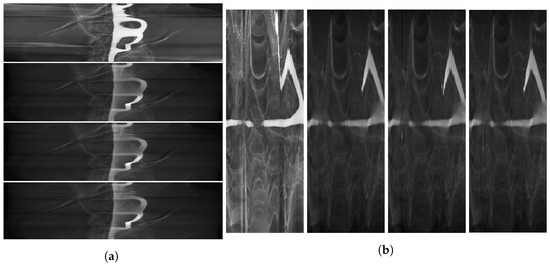

2. Materials and Methods

3. Results